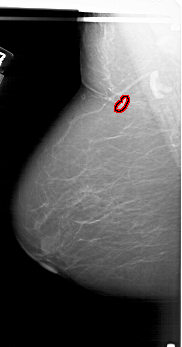

A_1805_1.RIGHT_CC

RIGHT_CC LINES 6571 PIXELS_PER_LINE 3256 BITS_PER_PIXEL 12 RESOLUTION 43.5 NON_OVERLAY